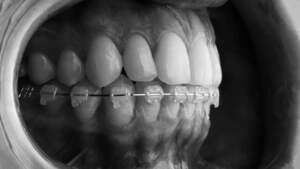

裏側矯正は舌側矯正、リンガル矯正とも言います。歯の裏側にブラケットとワイヤーを付けるため外からは見えない矯正方法で、「矯正をしていることを知られたくない」「目立たずに歯列矯正をしたい」という方におすすめです。

フルリンガルは上下全ての歯の裏側にブラケットを装着し、ワイヤーを通して歯を移動させる矯正方法です。

裏側矯正で使用する歯の裏側にブラケットとワイヤーを装着した歯のイメージ